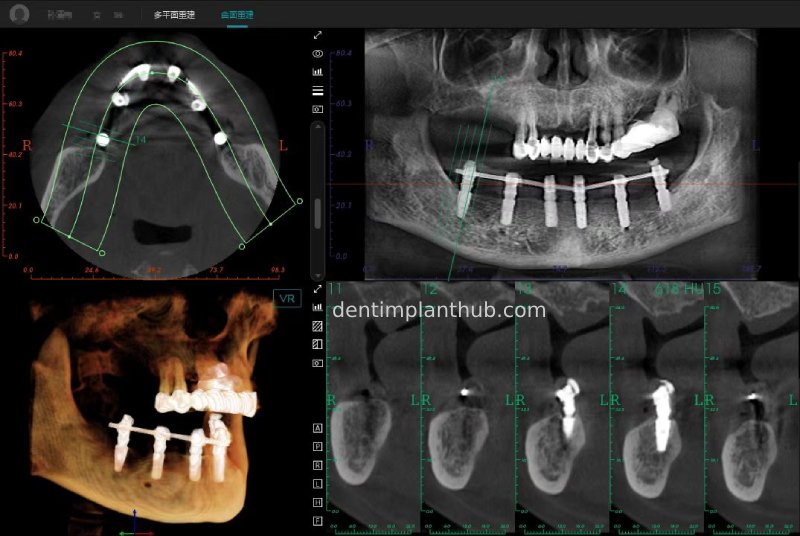

CBCT review results on 13 May '24

46

44

42

32

34

36

Maxillary condition as shown by CBCT on 13/5/24

16

14

12

22

24

26